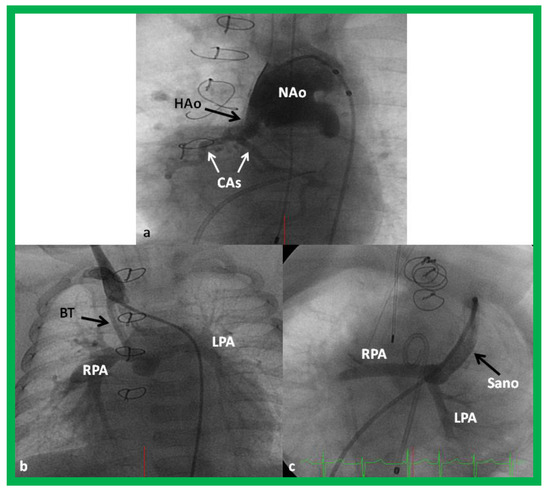

Figure 11.

Cineangiogrames demonstrating the Norwood procedure, showing the neoaorta (NAo) and hypoplastic old aorta (HAo). The latter supplies the coronary arteries (CAs) as shown in (a). A Blalock-Taussig (BT) shunt in seen in (b) and a Sano shunt in (c) from two other babies are also shown. This is Stage I of the Fontan procedure for infants with hypoplastic left heart syndrome. LPA, left pulmonary artery; RPA, right pulmonary artery. Reproduced from Reference [33].